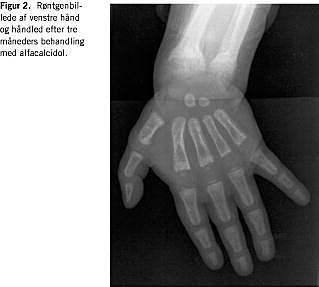

Behandlingen ændredes til 1 mg alfacalcidol. Herefter steg S-calcium-ion og total S-calcium, S-basisk fosfatase og S-PTH faldt (Tabel 1). Efter syv måneder var S-calcium og D-vitamin-stofskiftet normaliseret. Efter tre måneder var der radiologiske tegn på opheling (Figur 2), og efter knap et års behandling var der yderligere opheling af de påviste rakitisforandringer (Figur 3). Patienten og forældrene blev undersøgt for CYP27B1-genet (GeneDx lab. USA). Patienten var homozygot for en 7 bp-duplikation i exon 8 af CYP27B1-genet. Begge forældre var heterozygote for mutationen, havde normalt niveau af S-calcium, S-fosfat og P-1,25 dihydroxy-D-vitamin.